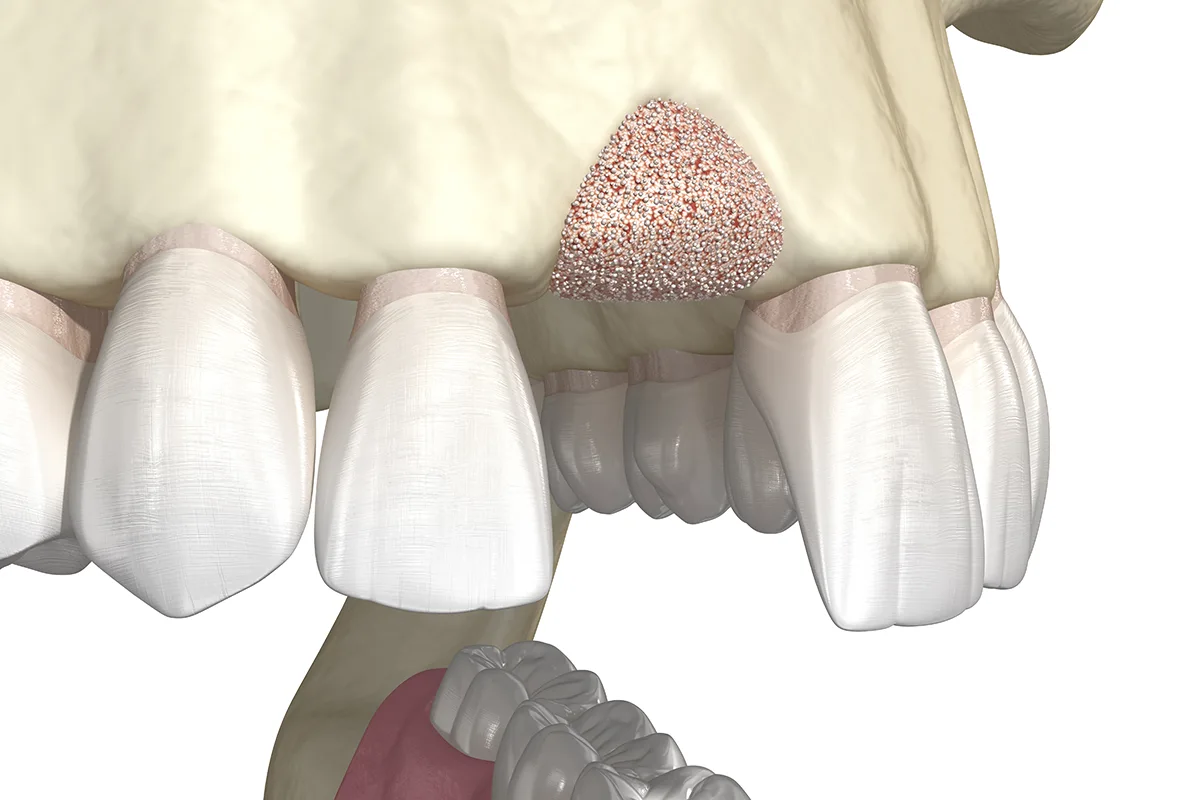

En estos casos es muy importante realizar una regeneración de hueso para conseguir resultados exitosos a largo plazo.

Además, tras realizar la extracción de un diente sabemos que se va a producir una remodelación ósea, perdiéndose gran cantidad de hueso en dicha zona. En muchas ocasiones es importante realizar un ROG (regenaramiento óseo guiado) para compensar la pérdida de hueso que va a acontecer y así poder optar a realizar posteriormente un tratamiento rehabilitador más conservador ya sea con implantes o con prótesis fija como puentes de cerámica.